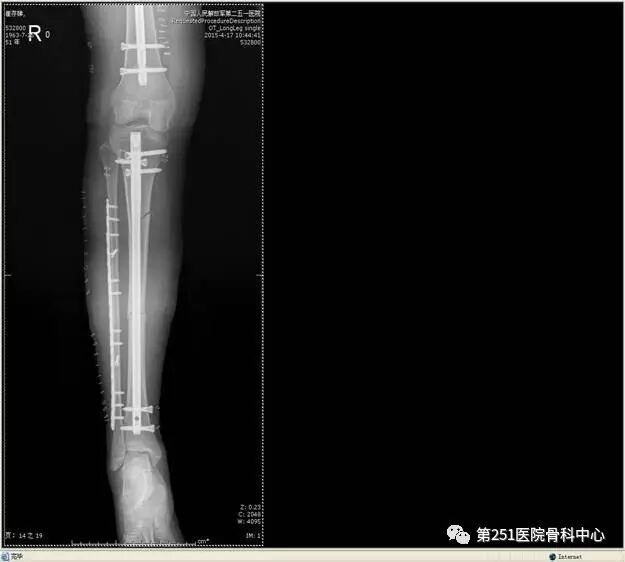

病例2:男性,44岁,车祸伤,双侧胫腓骨骨折(左侧)。